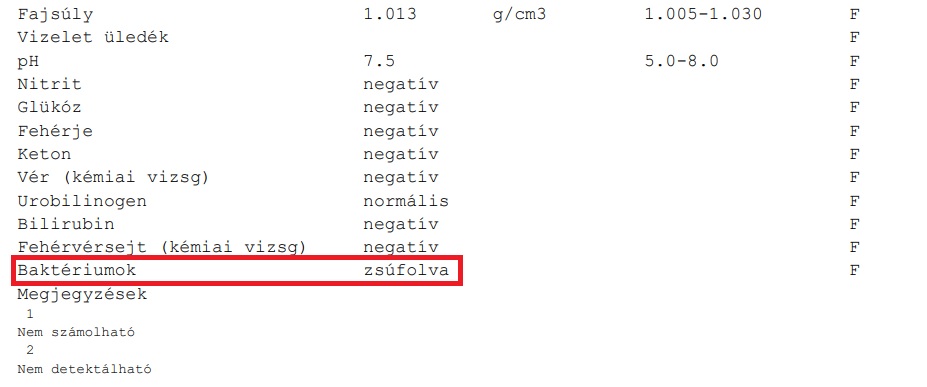

Konzultáció lett volna Dr. Tőke Judit leendő kezelőorvossal, de nem lehetett vele tárgyalni. A fiam elővette az 1 napos leletét, hogy megmutassa… mire Tőke Judit elkezdett hátrafelé futni, és kiabált: „Én nem láttam, nem láttam semmit, ugye látják, hogy nem láttam!”

Na ez a másik véglet. Az antiorvos, aki pánikba esik egy lelettől (na nem csak lelettől, hanem a súlyos felelősség terhétől). Hát kérem, ez olyan groteszk volt, hogy el nem hinné senki, hogy ilyen létezik. De ketten láttuk a fiammal. Tudtuk, hogy egy ilyen intézménybe a fiam nem léphet be többé. A magyar egészségügyben nincs lehetetlen! Közben a fiam vesefertőzése, vesemedence-gyulladása több mint 3 hónapja nem volt kezelve. A fenti leleten a Nitrit is jelzett, ami a fertőzés egyik legfontosabb markere és a vizelet tele volt baktériummal is! De a kezelőorvos elfutott… és bár előtte még felírta Zsolt telefonszámát, hogy visszahív minket a kezeléssel, befekvéssel kapcsolatban (80 nap késéssel az első nagy vérvizeléshez képest!!!), a hívás nem történt meg! Soha!